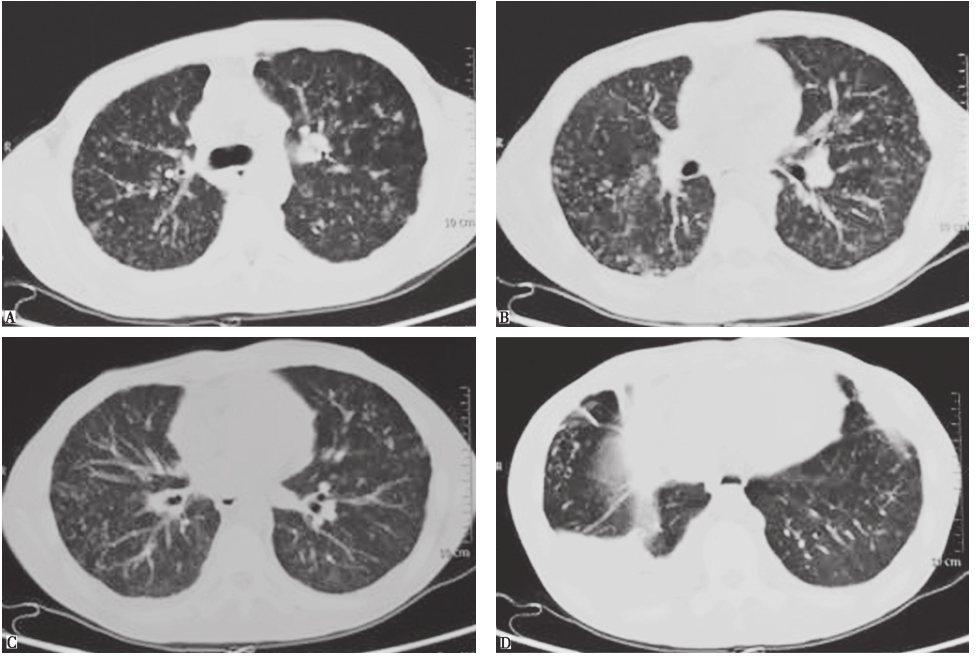

胸部CT:双肺弥漫对称性粟粒样结节灶及磨玻璃密度增高影,内见清晰支气管走行;双侧胸腔少量积液,心包见带状液性密度灶,纵隔未见明显肿大淋巴结;肝、脾大(图14)。

图14 复查胸部CT表现(2015-08-28)

胸部CT不同断面可见双肺弥漫对称性粟粒样结节灶及磨玻璃密度增高影,伴双侧少量胸腔积液